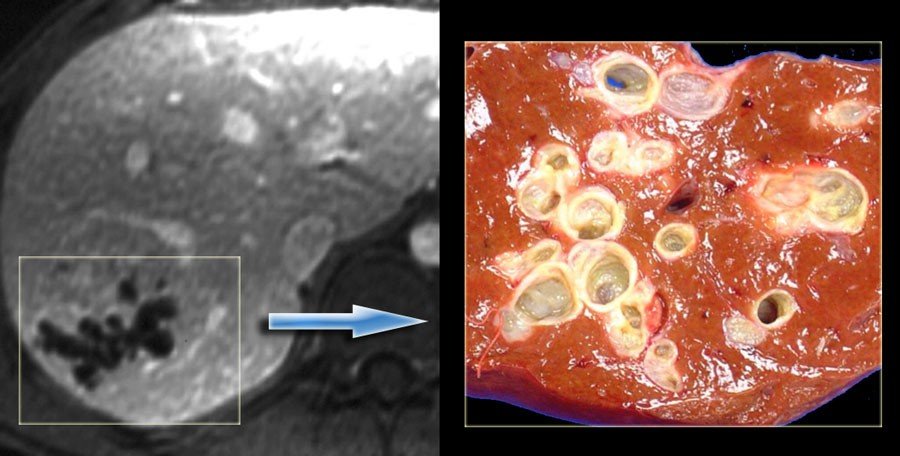

NEYROENDOKRİN TÖRƏMƏLƏRİN QARACİYƏRƏ METASTAZLARI

N.Y.Bayramov, R.A.Məmmədov

Tərifi

Orqan və toxumalarındakı yerli endokrin hüceyrələrindən (karsinoidlər) və mədəaltı vəzidəki (MAV) adacıq hüceyrələrindən inkişaf edən şişlərin qaraciyər metastazlarıdır.

Təsnifatı

Sayına görə

• təksaylı

• çoxsaylı

Mənbəyinə görə

• karsinoid (mədə-bağırsaq və digər)

• qeyri-karsinoid – adacıq (mədəaltı vəzi)

Hormonal aktivliyinə görə

• Funksional aktiv (funksional karsinoid, insulinoma, qastrinoma, qlükaqonoma, somatostatinoma, VİP-oma, ACTH-oma, PTH-oma, GRF-oma)

• qeyri-aktiv

Bədxassəlik dərəcəsinə görə (ÜST təsnifatı)

• xoşxassəli

• bilinməyən

• aşağı dərəcə bədxassəli

• yüksək dərəcə bədxassəli

Ümumi xarakteristika

• Neyroendokrin törəmələr (NET), orqan və toxumalarındakı yerli endokrin hüceyrələrindən və mədəaltı vəzidəki (MAV)adacıq hüceyrələrindən inkişaf edən şişlərdir.

• Bunlara APUD-omalar da deyilir

• Klassik olaraq NET-lər iki qrupa bölünür: karsinoid və qeyri-karsinoid şişlər.

• Tərkibində neyronal enolaza enziminin olması sinir mənşəli olduqlarını göstərir.

• Hormonal aktiv və ya qeyri-aktiv formaları ola bilir.

• NET-lərin bəd və xoşxassəli formaları sitoloji və histoloji cəhətdən fərqlənmir, bədxassəliyin yeganə əlaməti metastazların olmasıdır.

• NET-lərin hamısında xromoqrafin A və neyron spesifik enolaza tapılır ki, bu da diaqnozu dəqiqləşdirə bilir.

Gedişi

• NET metastazları yavaş böyüyən, kimyaterapiyaya az həssas törəmələrdirlər, adətən hipervaskulyar olurlar və sürətli qan axınına sahibdirlər.

• NET-in təbii gedişinə təsir edən ən önəmli amillər qaraciyərə metastaz, metastazların sayı və müalicədir: 5 illik yaşam metastaz olmayan hallarda 90-100%, metastaz olduqda 30-40%,  rezeksiyadan sonra 70%-ə çata bilir.

• Dəqiqləşdirmək üçün klinik əlamətlərlə yanaşı endokrin müayinə, tomoqrafiya və ssintoqrafiya aparılır.

• NET-in qaraciyər metastazlarının xarakterik xüsusiyyəti hipervaskulyar olmasıdır ki, bu da Doppler müayinəsində intensiv axın şəklində, kontrastlı müayinələrdə isə arterial fazada kontrastlaşma və venoz fazada yuyulma əlaməti ilə təyin edilir.